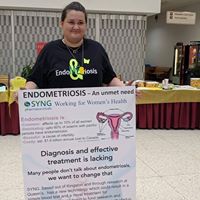

Fairy Menstrual Cups  Endometriosis and me